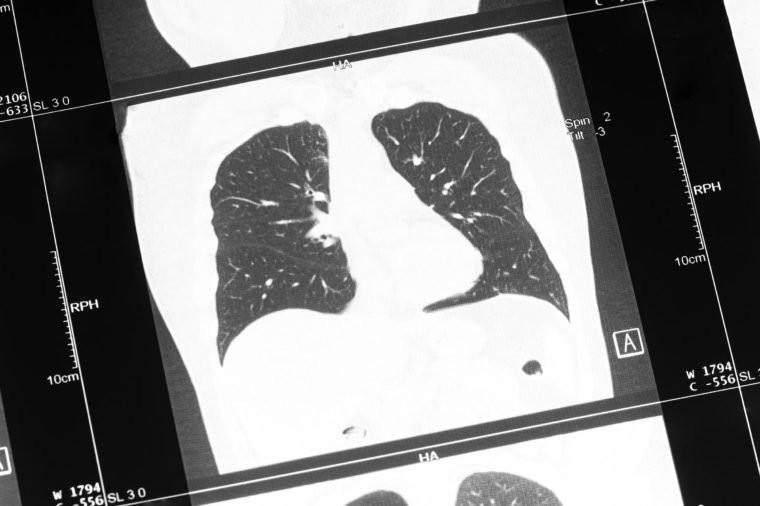

Các bệnh ung thư đường hô hấp: Ung thư khí quản, phế quản và phổi gây ra 1,7 triệu ca tử vong trong năm 2016, theo WHO và đứng thứ sáu trong danh sách những bệnh gây tử vong hàng đầu thế giới.